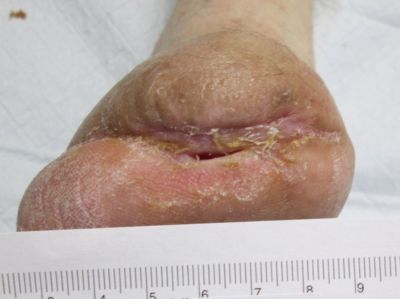

Assessment during her first visit to the clinic revealed trophic skin changes of chronic ischemia, and non-palpable dorsal pedis (DP) or posterior tibial (PT) pulses. Capillary refill was sluggish. The contralateral limb presented similarly. The periwound was boggy and mottled, and the wound bed was a dry, dull red. Bone from the first metatarsal was visible, but appeared viable. Both bone and tissue specimens were taken for PCR (polymerase chain reaction) plus culture and sensitivity, of which only the tissue revealed significant growth of pathogens; osteomyelitis was not suspected at this juncture. The patient's wound was covered with a moisture retentive dressing and she was immediately referred to the lower extremity vascular specialist at the neighboring heart institute, where she underwent successful, albeit complex, vascular intervention.

Within an 8 week period, she received targeted oral antimicrobial therapy and conservative wound care inclusive of sharp debridement, strict offloading, and dressings to promote moisture and healthy tissue proliferation in the wound bed. The patient-centered plan also included glucose control, dietary modification to include protein supplementation, and smoking cessation. Despite all the above measures, the wound continued to probe to bone, and showed little signs of healing.